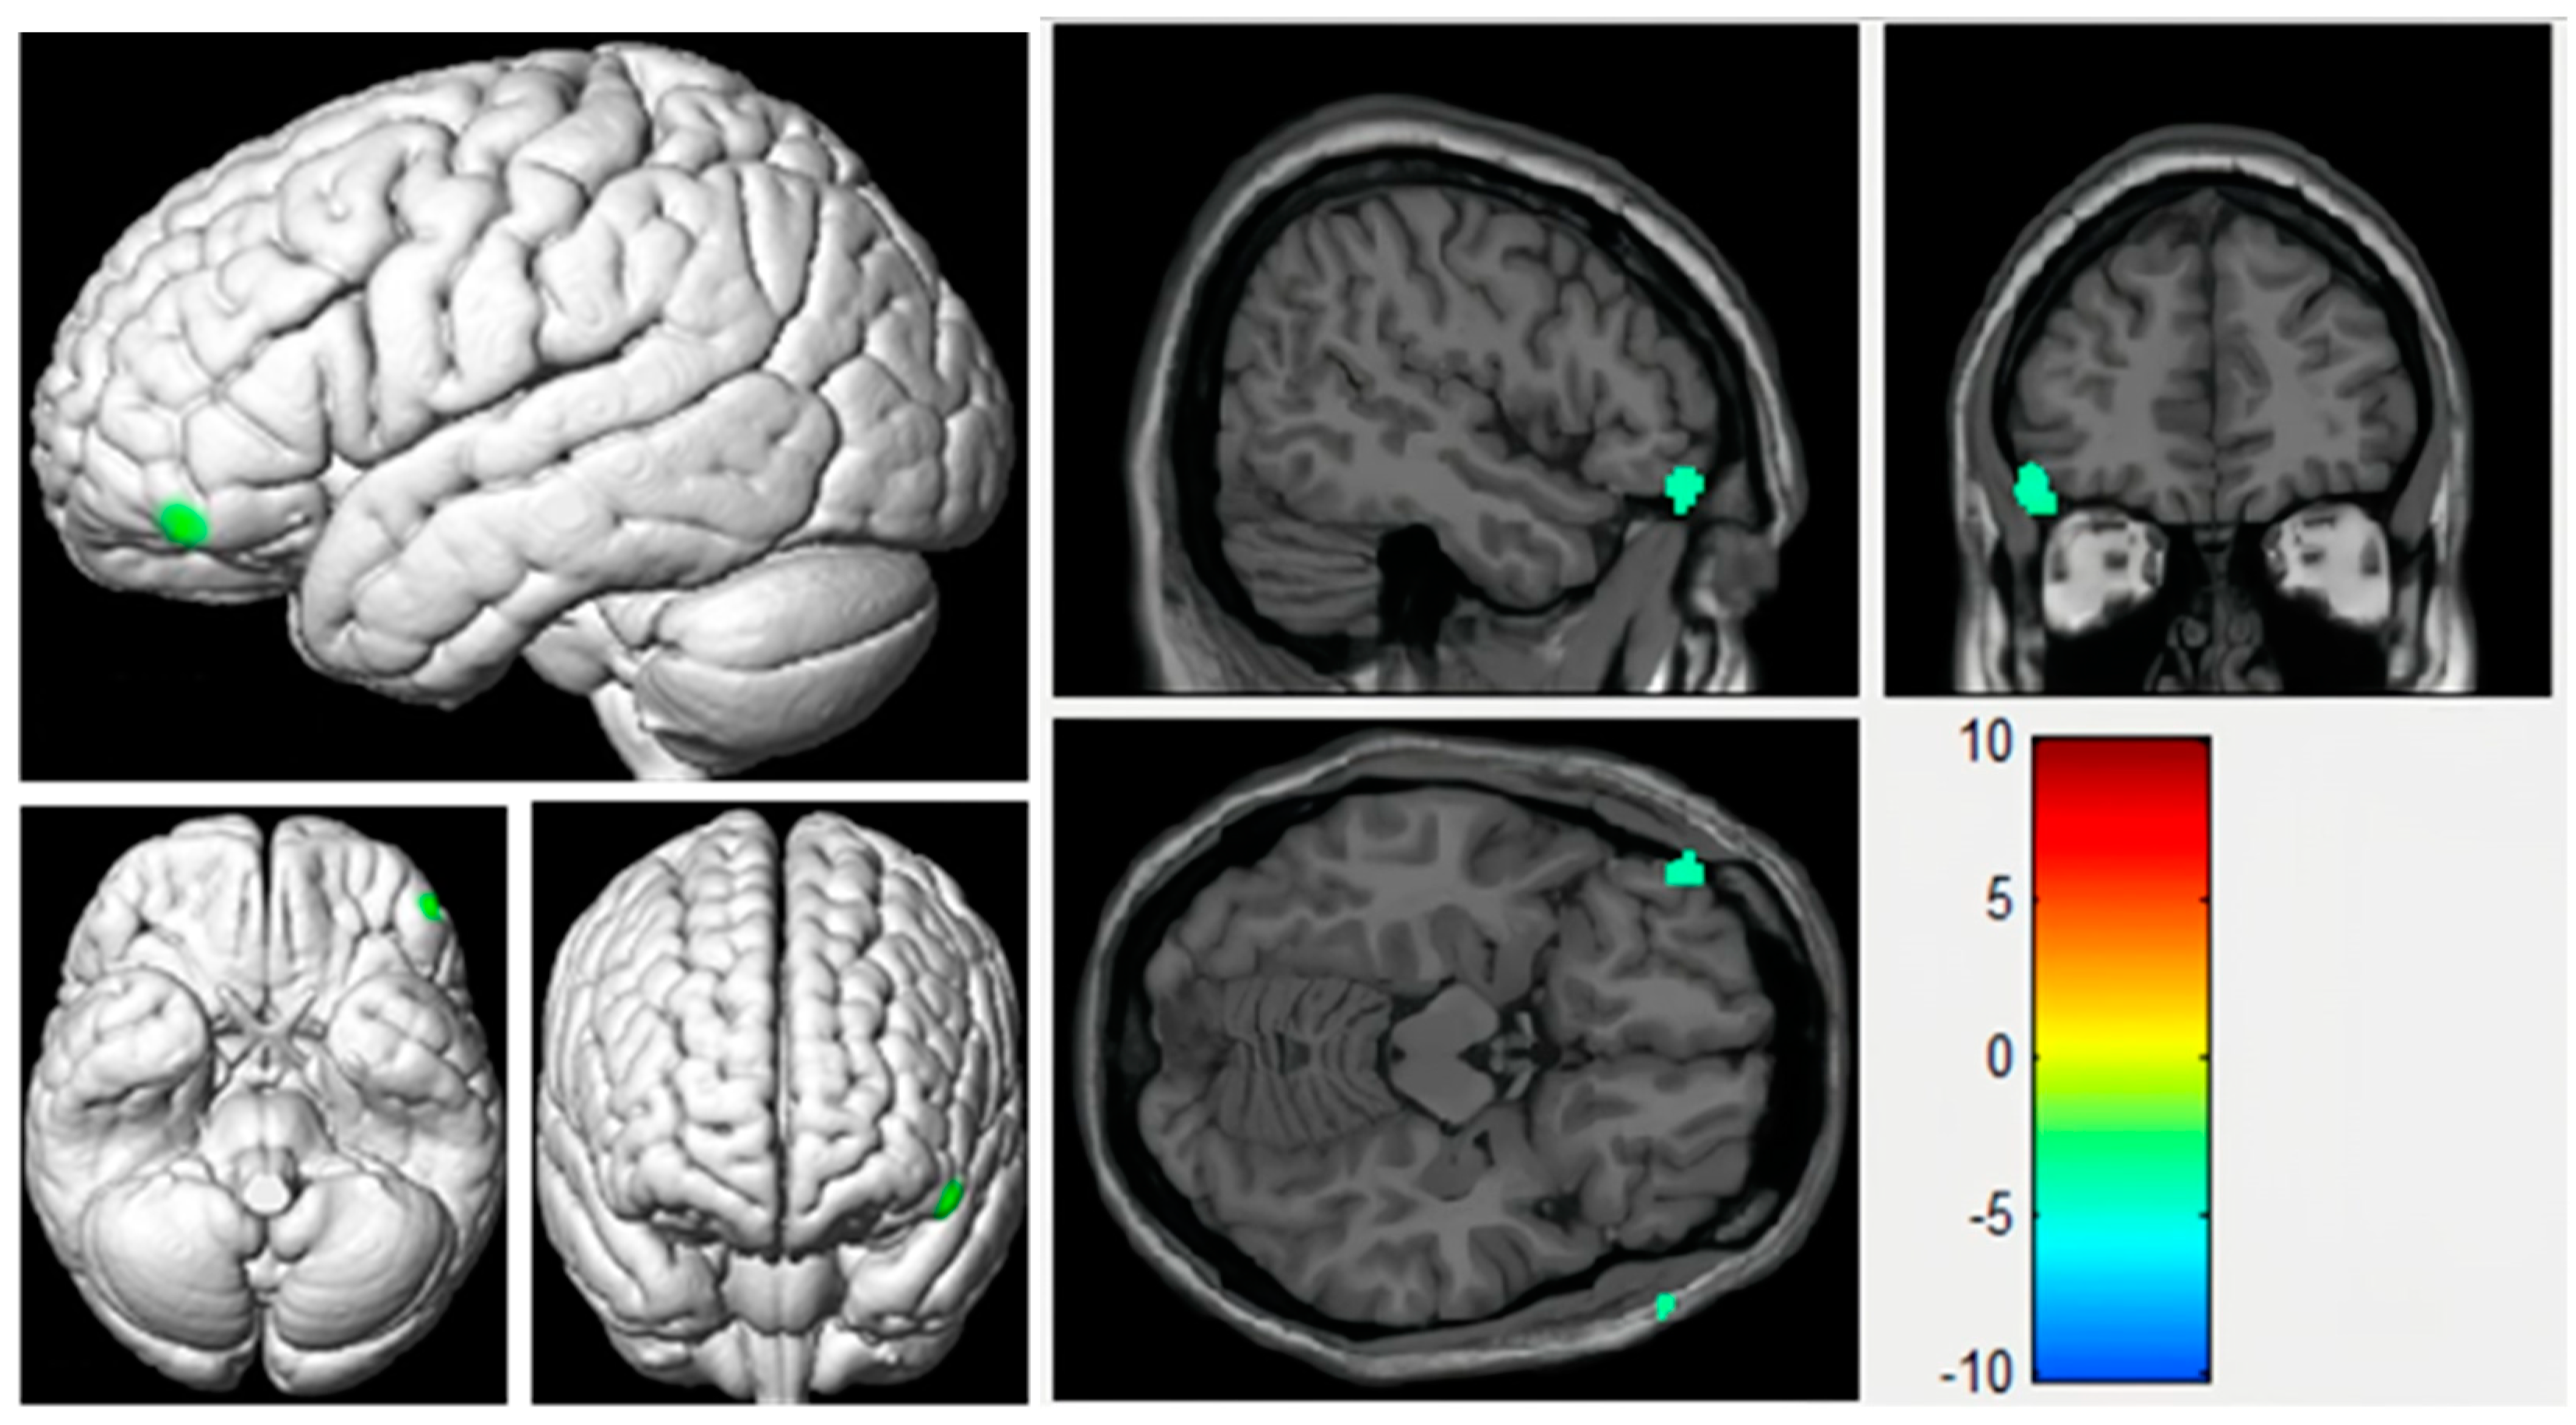

| Brain Area | Peak MNI Coordinate | Cluster Size | Statistical Value (T) | ||

|---|---|---|---|---|---|

| x | y | z | |||

| Right anterior cingulate gyrus | 3 | 30 | 9 | 11 | 3.5365 |